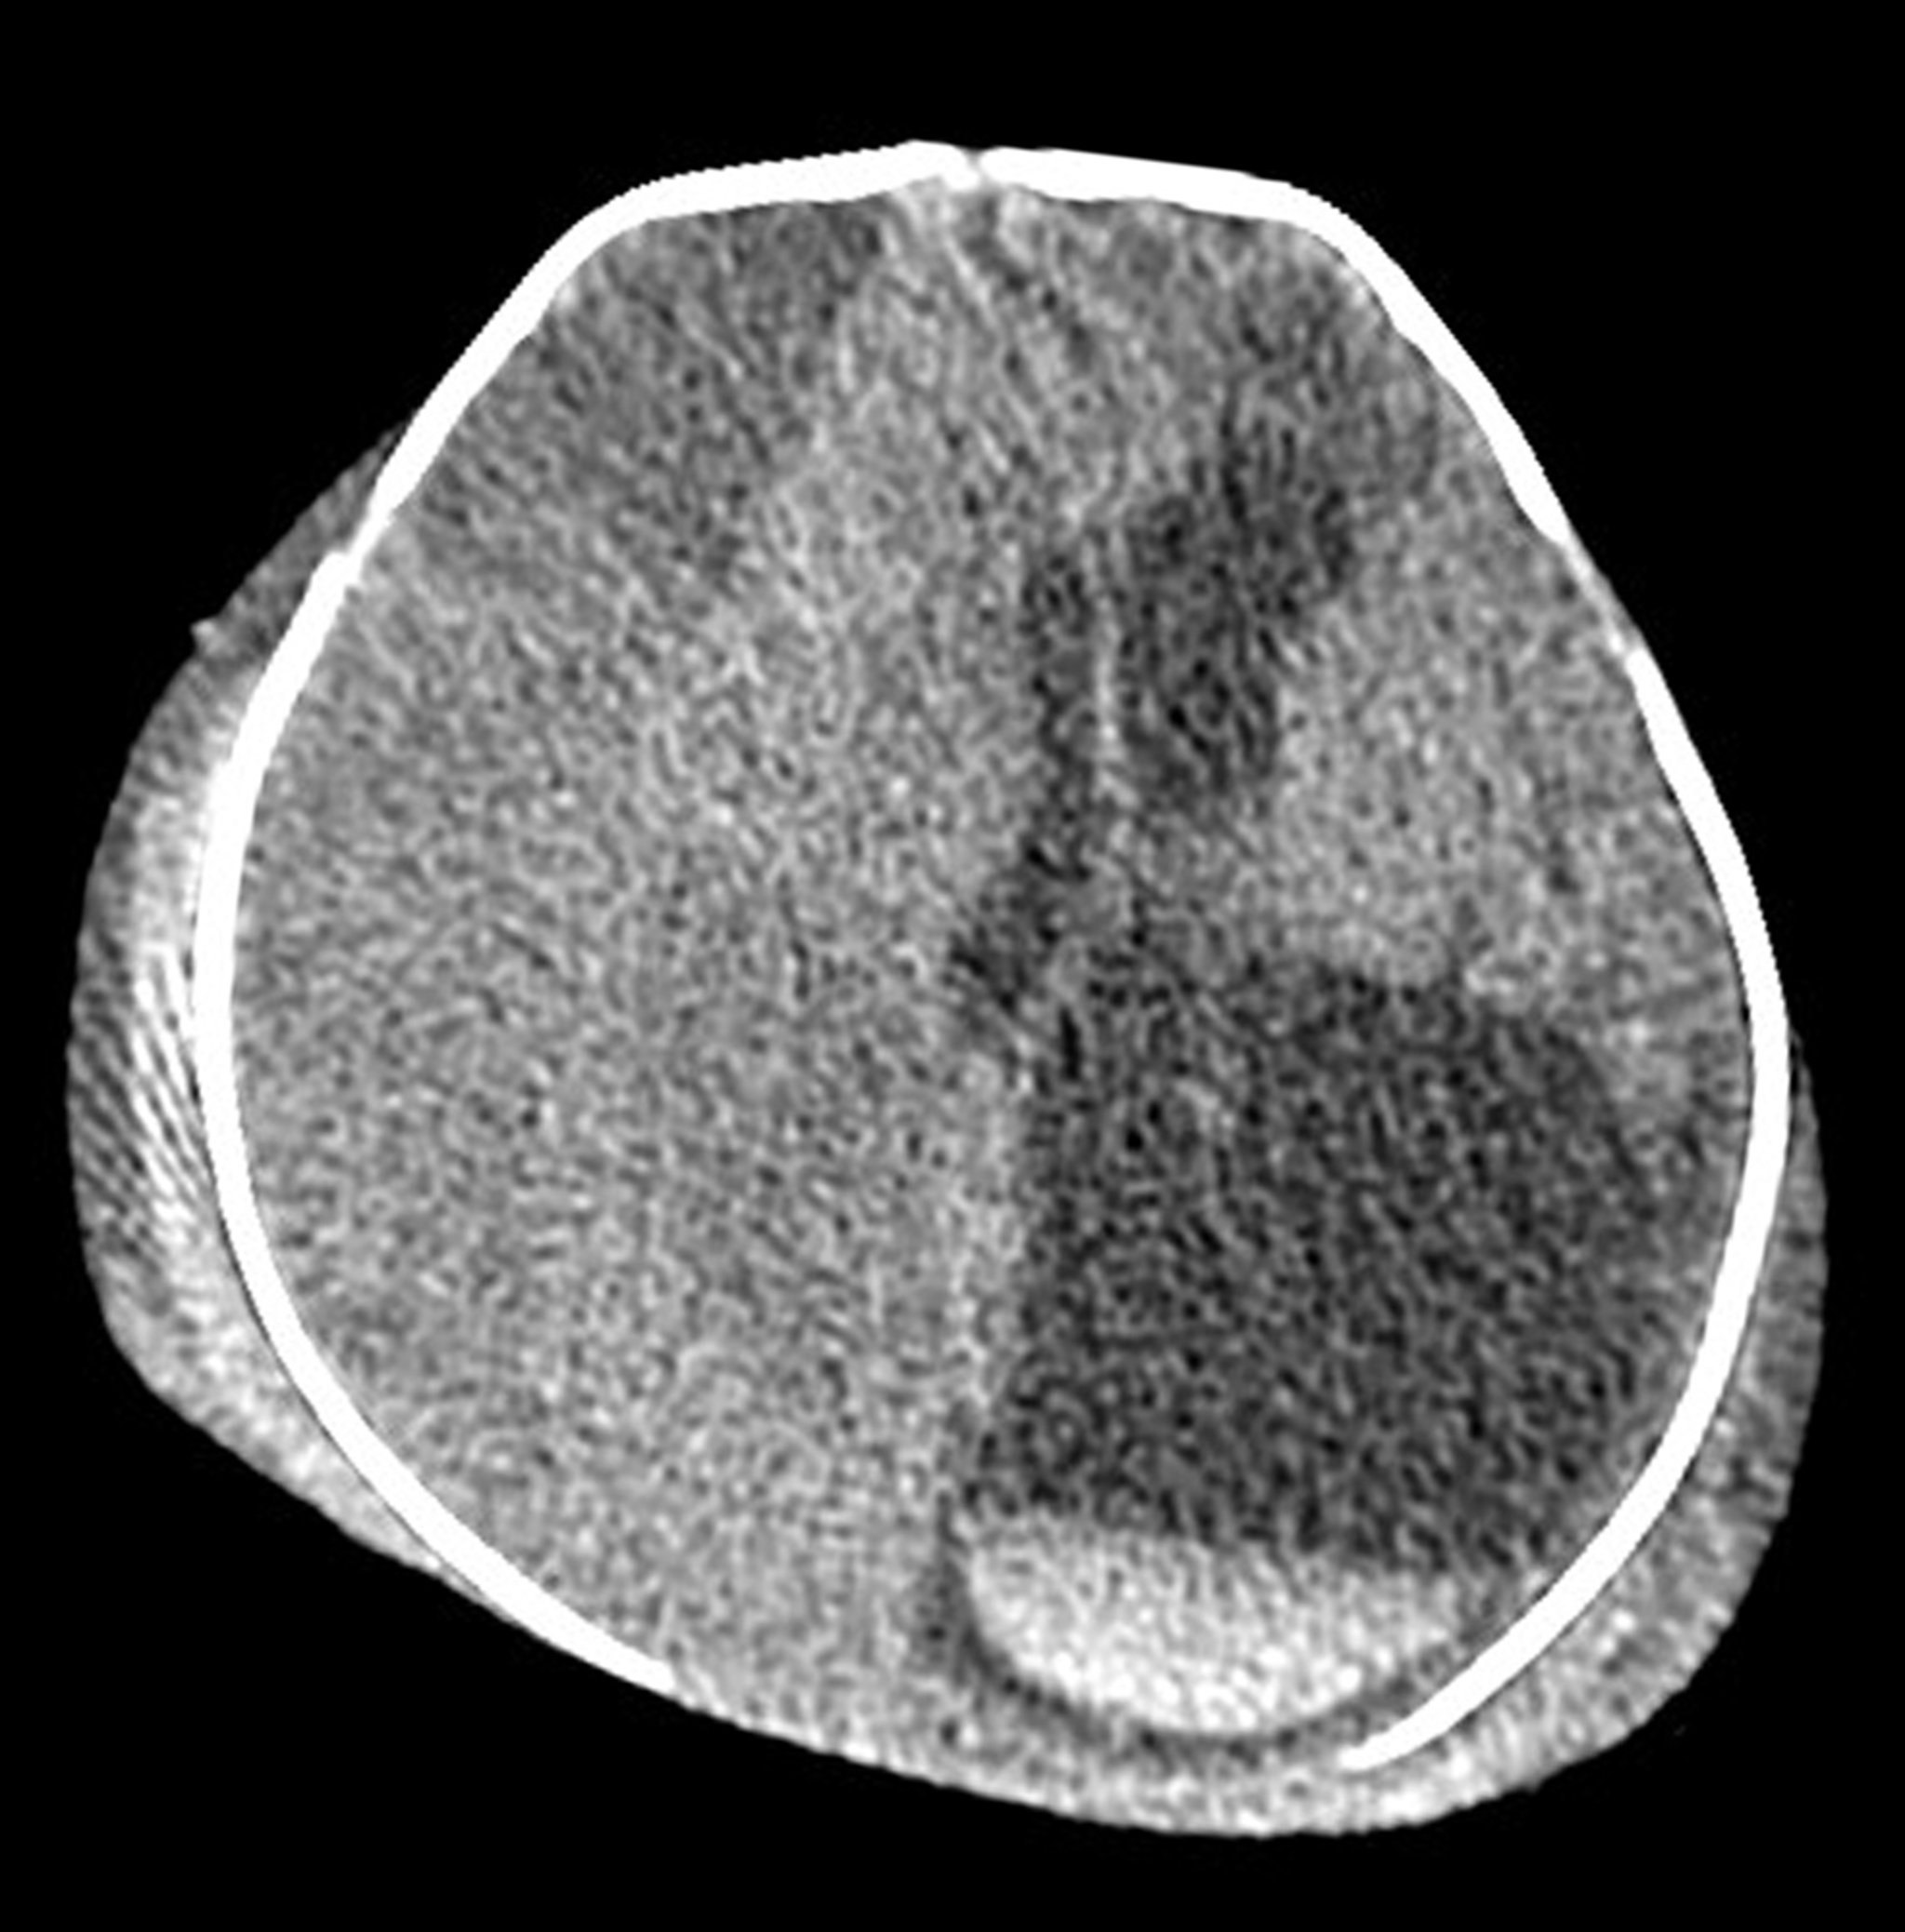

Обширные родовые травмы у новорожденных (компьютерная томография)

На этом аксиальном (поперечном) КТ-снимке головы новорожденного видны обширные экстракраниальные и внутричерепные повреждения, вторичные по отношению к тяжелой родовой травме. В волосистой части головы имеется двусторонний отек/гематома. Это очень большая изоденсивная (подострая) субдуральная гематома вдоль правого полушария головного мозга, являющаяся причиной развития вклинения головного мозга по средней линии. Эта гематома приводит к увеличению левого бокового желудочка. В правом нижнем углу снимка видны критические наслоения крови на дне левого бокового желудочка (белое вещество с прямой линией).